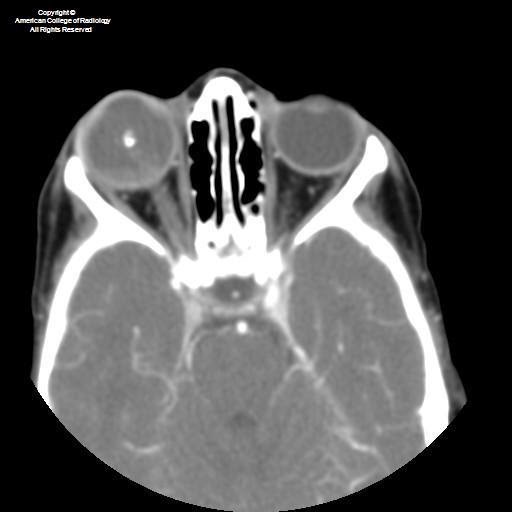

Retinoblastoma for medical students Dr. Khalil AlSalem